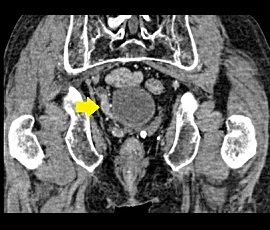

[自然右腎盂外溢流(尿管がん)] 手術:腹腔鏡補助下右腎尿管全摘除術

CT画像(矢印:水腎症,矢頭:液体貯留)

CT画像(矢印:腫瘍性病変)